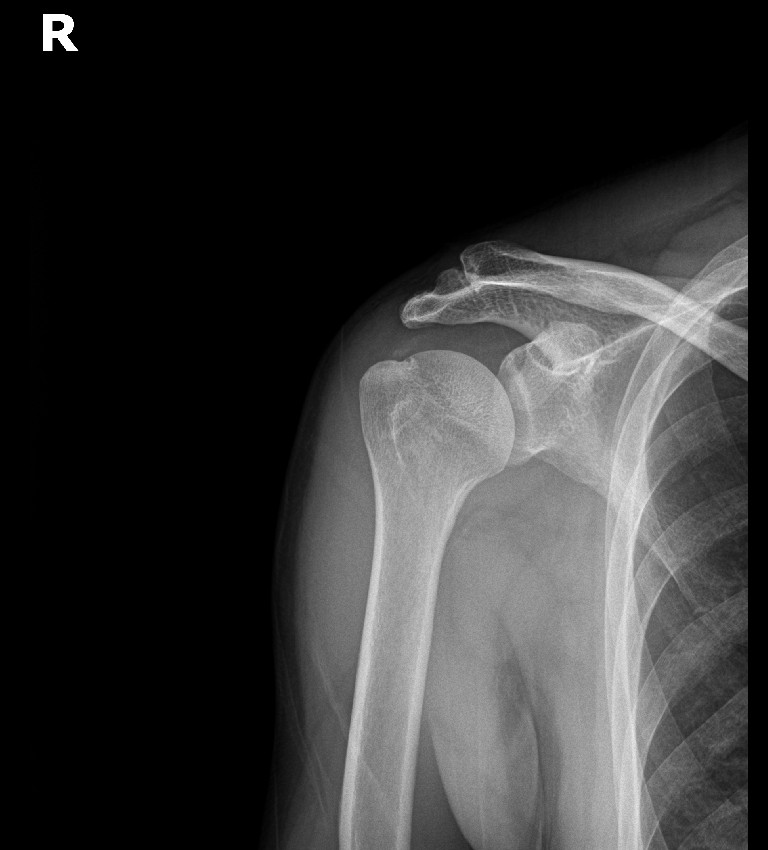

Step 6: 최종 확인 및 마무리

초음파와 X-ray로 석회 제거 확인 후 마무리합니다.

초음파: 석회 부위 확인

X-ray: 석회 완전 제거 확인

진단:

X-ray: 약 1.3cm 석회 (휴지기)

시술 직후 X-ray에서 석회 완전 제거 확인